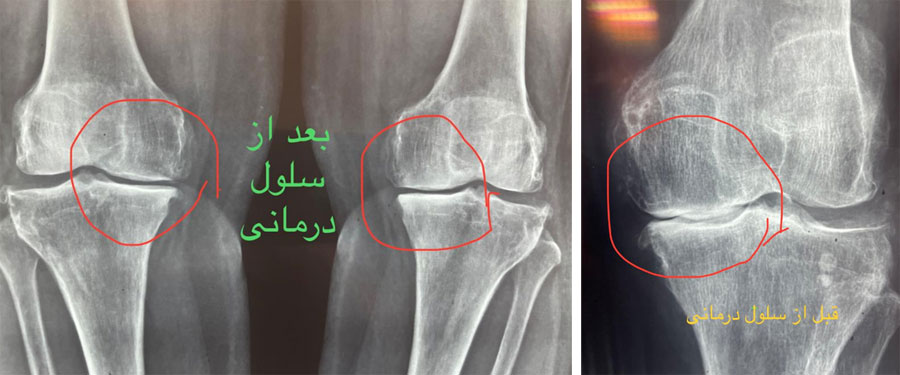

سلول درمانی زانو قبل و بعد